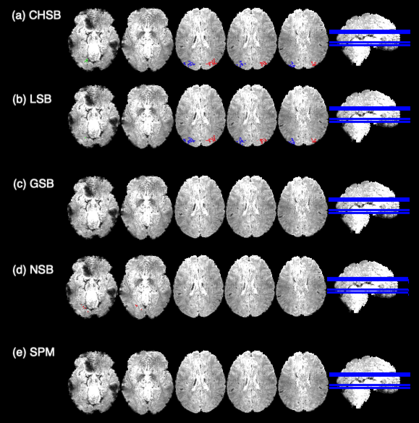

In this paper, we introduce a new Bayesian approach for analyzing task fMRI data that simultaneously detects activation signatures and background connectivity. Our modeling involves a new hybrid tensor spatial-temporal basis strategy that enables scalable computing yet captures nearby and distant intervoxel correlation and long-memory temporal correlation. The spatial basis involves a composite hybrid transform with two levels: the first accounts for within-ROI correlation, and second between-ROI distant correlation. We demonstrate in simulations how our basis space regression modeling strategy increases sensitivity for identifying activation signatures, partly driven by the induced background connectivity that itself can be summarized to reveal biological insights. This strategy leads to computationally scalable fully Bayesian inference at the voxel or ROI level that adjusts for multiple testing. We apply this model to Human Connectome Project data to reveal insights into brain activation patterns and background connectivity related to working memory tasks.